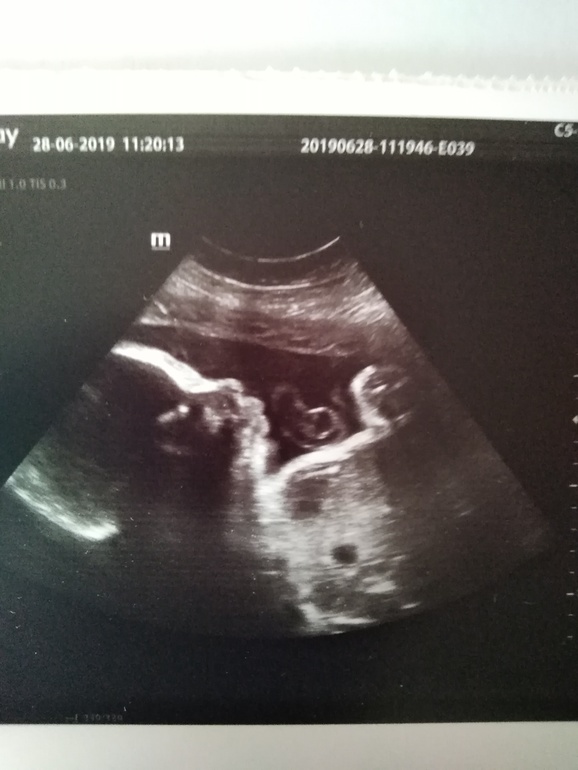

Прошла 3 скрининг в 32 недели. Вес ребёнка 2100, рост 45 см. Параметры все в норме. Рубец на матке тоже более чем хорош 4,3 мм. Главное чтобы ситуация с ним не менялась. Сделали наконец то фото ребенка

Вот такой вот чудесный мальчишка. Вышел очень серьёзным.